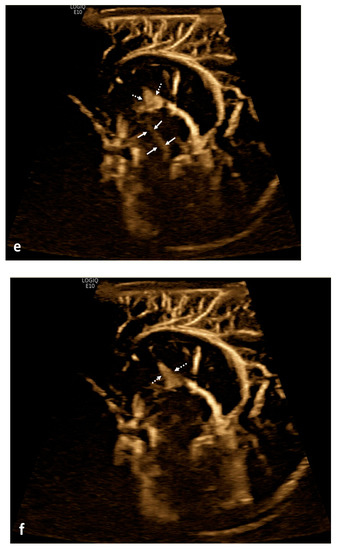

Table 3.

Current and emergent imaging protocols used for the evaluation of cerebrospinal fluid flow.